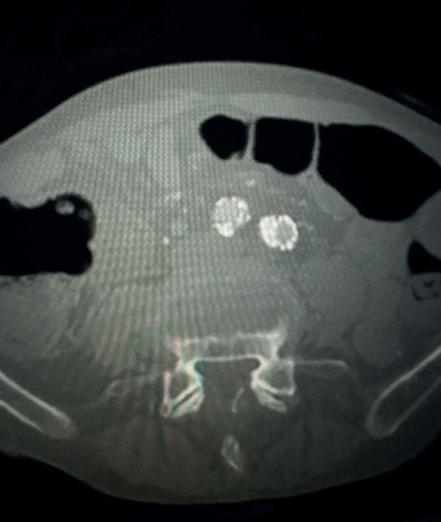

Case 2: The Shockwave M5+ tackles 90% stenosis of the distal SFA

The patient is a 75-year-old man with a history of hypertension, hyperlipidemia, CAD, chronic kidney disease and diabetes mellitus, who presents with a non-healing wound of the right lower extremity for three months.

He had undergone diagnostic work—his ankle-brachial index (ABI) was found to be 0.73 with a toe pressure of 50mmhg, and a duplex ultrasound revealed a densely calcified superficial femoral artery (SFA) stenosis of 90%.

He was taken to the cath lab and underwent a right lower-extremity arteriogram. This confirmed a 90% stenosis of the distal SFA, with normal three-vessel run off.

Due to the heavy calcium, we opted for a Shockwave M5+ 6x60mm and delivered 200 pulses to the lesion. There was no appreciable residual stenosis at the completion of the procedure, and his post-procedure ABI improved to 1.

Figure 1. Pre-procdural CTA Figure 4. Graft delivery Figure 1. Pre-procedural angiogram Figure 2. Pre-procedural angiogram Figure 5. Final angiogram Figure 2. IVL treatment angiogram Figure 3. Post-IVL angiogram Figure 6. Post-procedural CTA Figure 3. Final angiogram